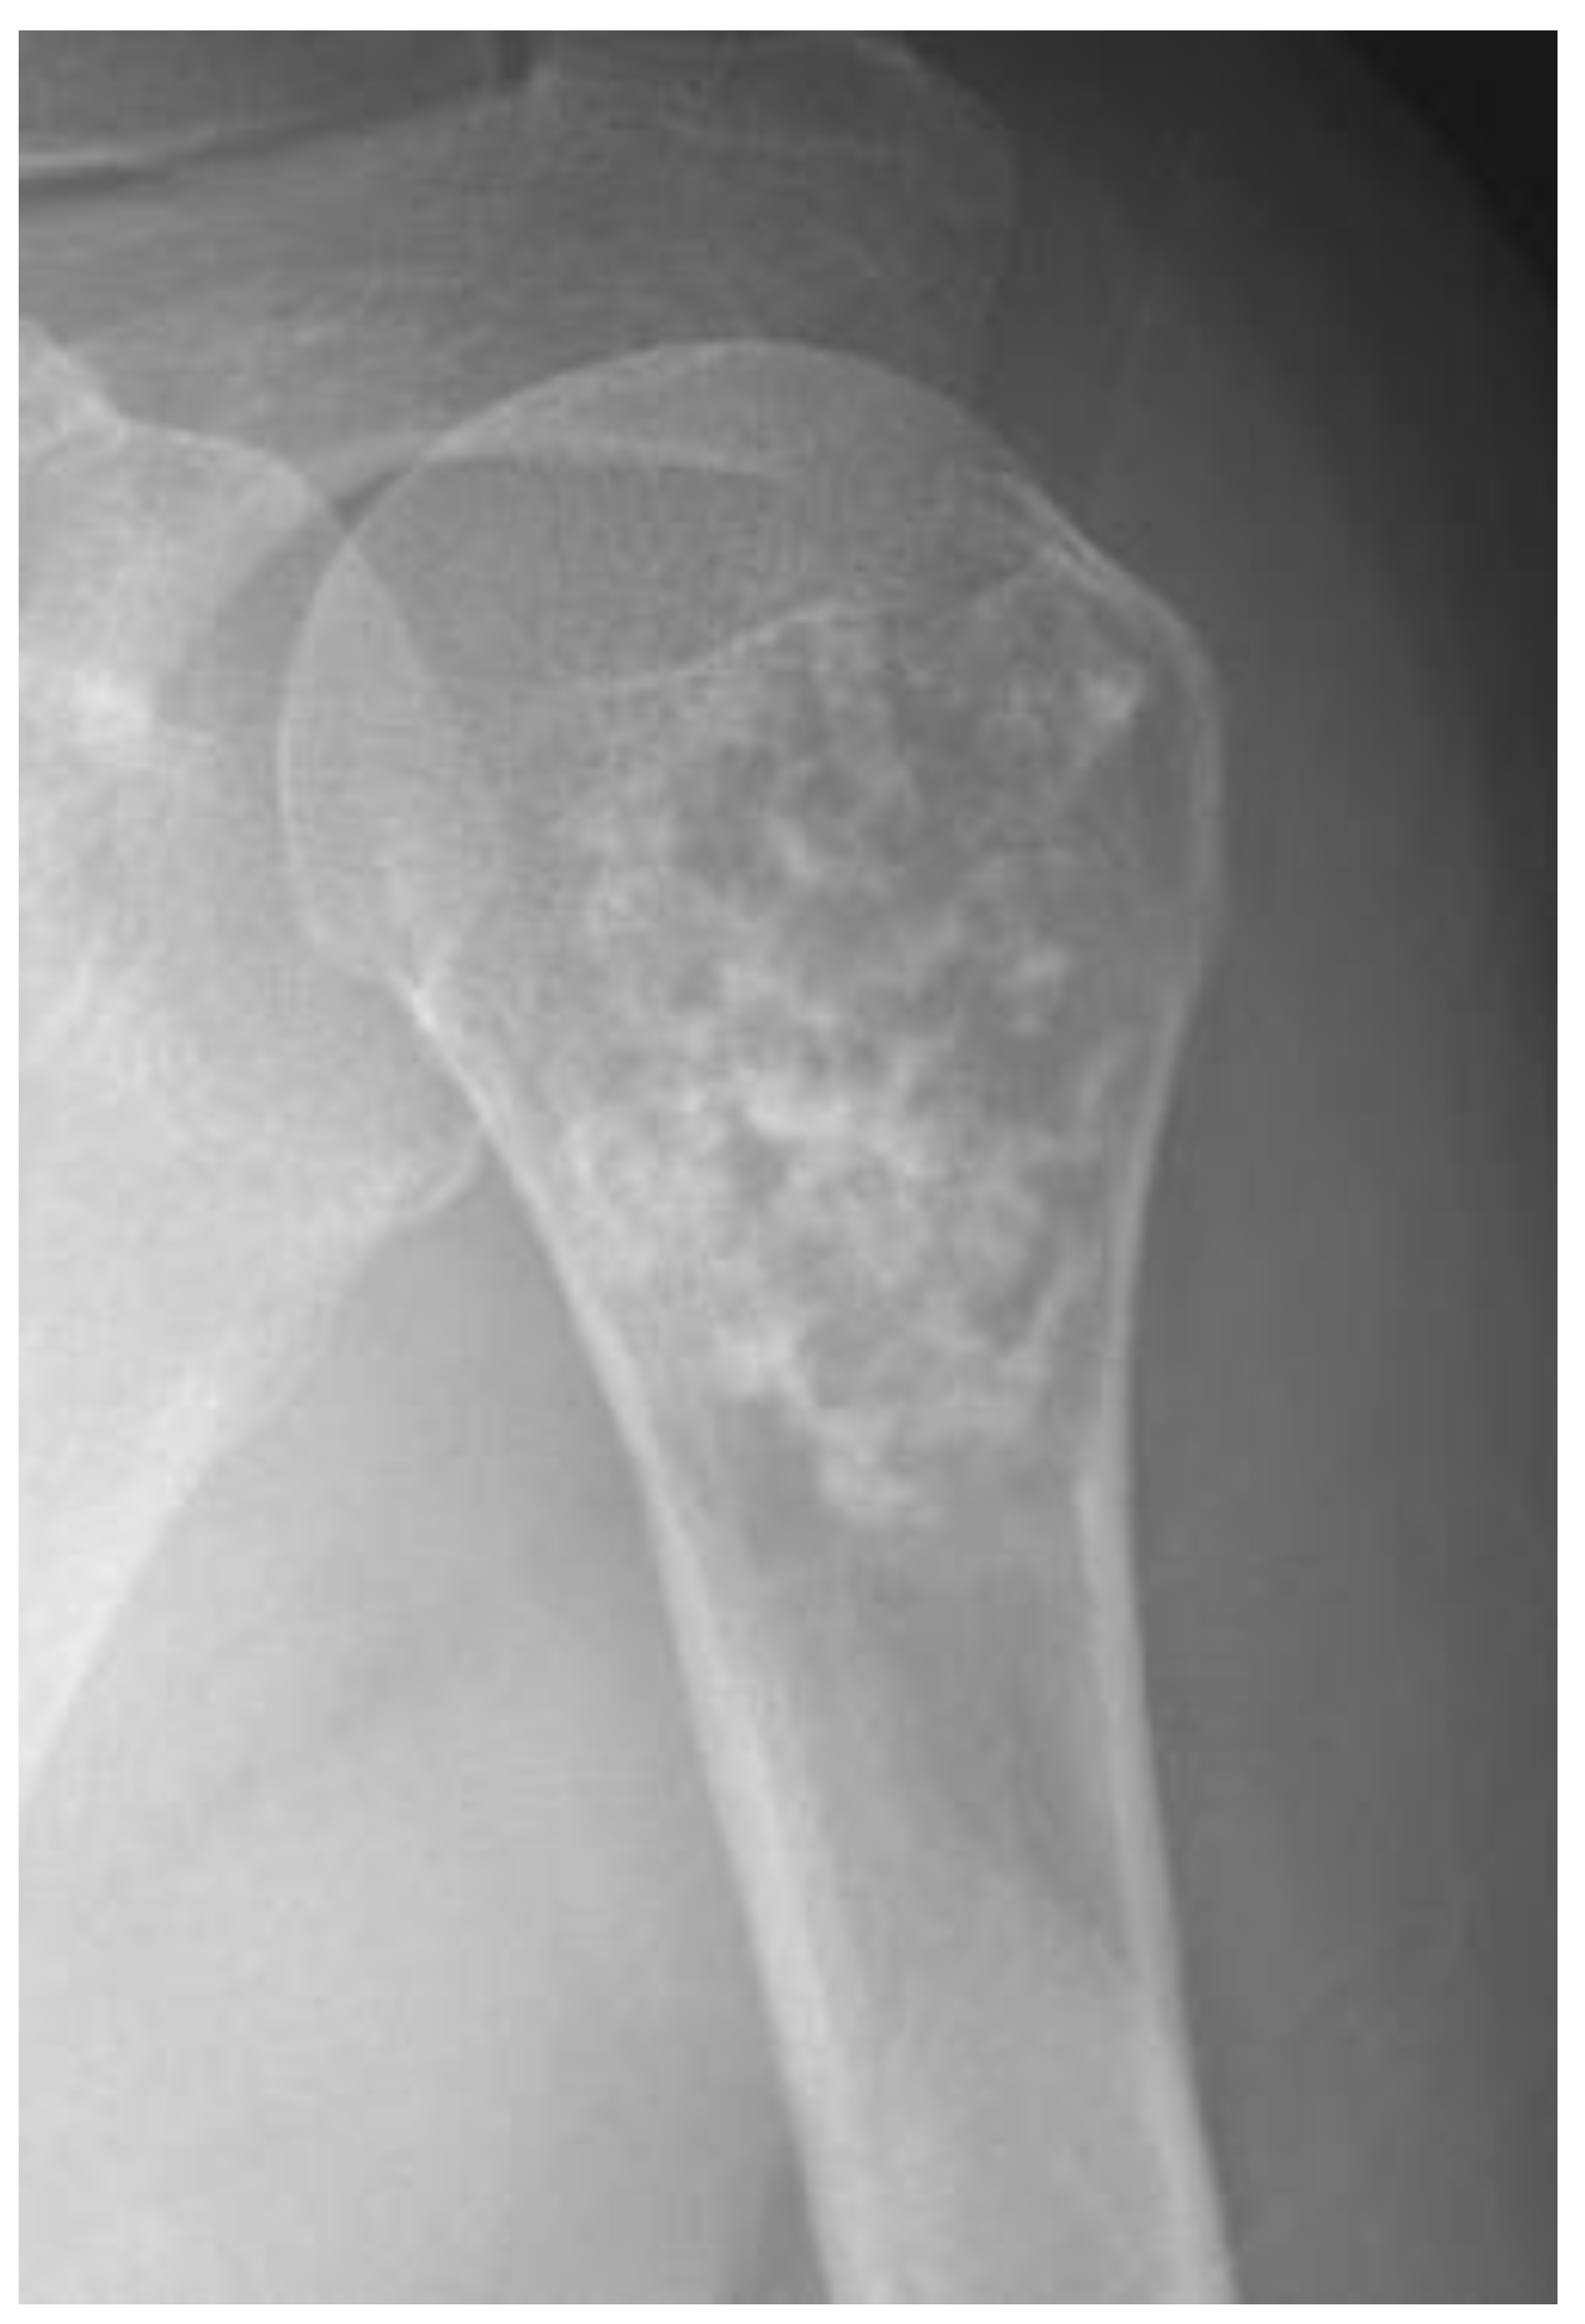

- Collins, M.S.; Koyama, T.; Swee, R.G.; Inwards, C.Y. Clear cell chondrosarcoma: Radiographic, computed tomographic, and magnetic resonance findings in 34 patients with pathologic correlation. Skelet. Radiol. 2003, 32, 687–694. [Google Scholar] [CrossRef]

- Kumar, R.; David, R.; Cierney, G., 3rd. Clear cell chondrosarcoma. Radiology 1985, 154, 45–48. [Google Scholar] [CrossRef]

- Bagley, L.; Kneeland, J.B.; Dalinka, M.K.; Bullough, P.; Brooks, J. Unusual behavior of clear cell chondrosarcoma. Skelet. Radiol. 1993, 22, 279–282. [Google Scholar] [CrossRef]

- PPresent, D.; Bacchini, P.; Pignatti, G.; Picci, P.; Bertoni, F.; Campanacci, M. Clear cell chondrosarcoma of bone. Skelet. Radiol. 1991, 20, 187–191. [Google Scholar] [CrossRef] [PubMed]